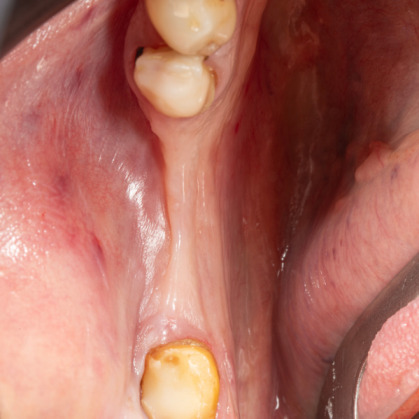

İmplant etrafındaki kemik açıklığını kemik grefti ile tedavi ettiğimiz vakamızdan biri